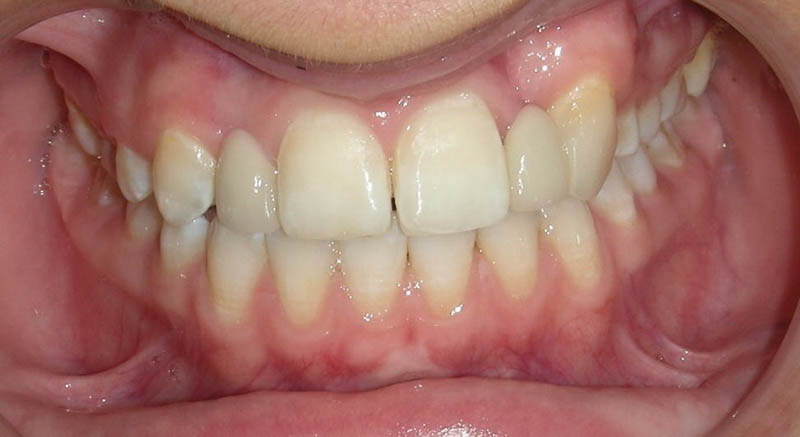

A doua etapă a tratamentului a fost amânată până în aprilie 2006, când pacienta a împlinit vârsta de 11 ani şi 5 luni. În acel moment, fetiţa prezenta erupţie şi dezvoltare radiculară adecvată, astfel că aparatele fixe aplicate acum n-ar fi purtate o perioadă îndelungată. Ocluzia inversă frontală şi angrenajul invers lateral fuseseră corectate; totuşi, exista o diastemă mare, în principal cauzată de lipsa incisivilor laterali superiori (fig.3). În acest moment, radiografia panoramică relevă anodonţia incisivilor laterali maxilari şi a premolarului secund drept mandibular, o anatomie redusă a rădăcinilor incisivilor centrali superiori, incluzia caninului superior stâng şi dezvoltarea întârziată a rădăcinii celui de-al doilea premolar inferior (fig. 4).

Faza a II-a a debutat cu un aparat fix ortodontic 2×2, aplicat la nivelul primilor molari şi al incisivilor centrali maxilari, în vederea derotării primului molar drept. Ulterior, s-au aplicat aparate fixe pe întreaga arcadă, cu scopul de a controla erupţia dentară. Caninul stâng superior a fost descoperit chirurgical într-o fază timpurie de tratament şi a durat aproximativ 18 luni pentru a putea fi aliniat pe arcadă (fig. 5). Pacienta a purtat elastice de clasa a doua pe partea stângă pentru a tracţiona caninul în poziţie; cu toate acestea, acest dinte nu a ajuns niciodată în raportul de clasa I, neutral, dorit.